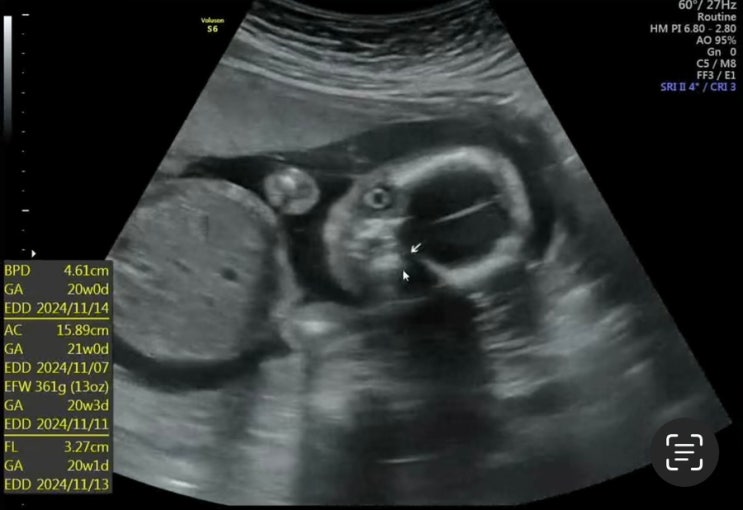

8. 대구 수성구 효성병원(#8. 19주 3일 초음파진료) 및 보험적용안내 후기

2024년 6월 27일 목요일 - 17주 세컨 병원에서 빤짝이 만나고 왔었는데 분만병원 정기적으로 가는날! ㅎㅎ ...